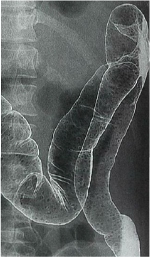

<注腸造影>

(96回医師国家試験A26)